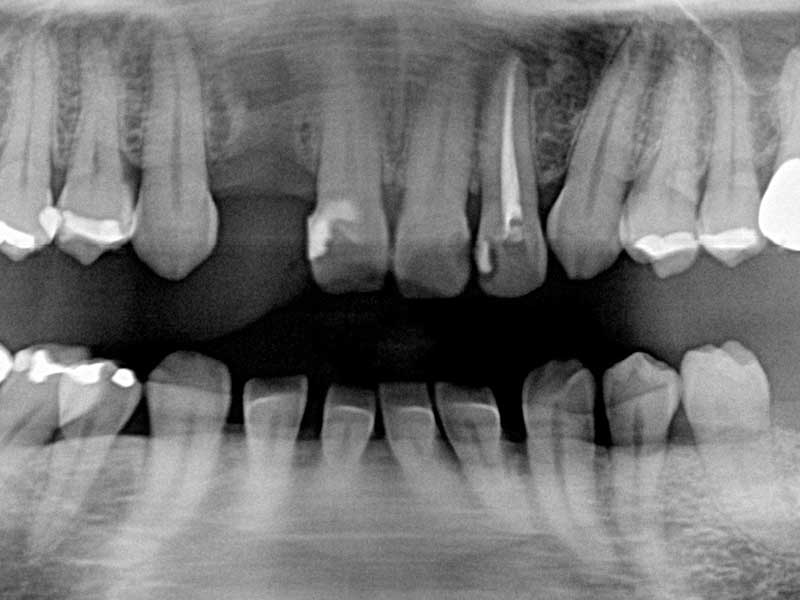

術前(レントゲン写真)